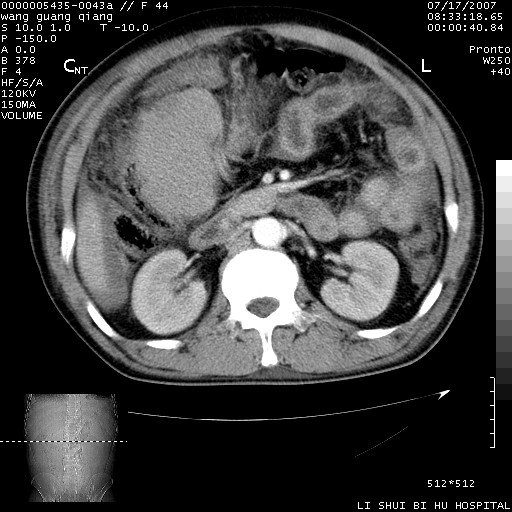

以下是引用dyqct在2007-7-18 10:46:00的发言:[br]胆囊明显增大,壁增厚,明显强化;后下方见大片高密度区,ct值68hu,无强化,周围见多数条纹状高密度影,边界不清。双膈下间隙、肝肾隐窝见带状及片状低密度区。[br]右侧胸壁后缘亦见新月形水样密度区。[br]考虑:1、急性胆囊炎伴周围出血;[br] 2、少量腹水、右侧少量胸腔积液。[br][br][本贴已被 dyqct 于 2007-7-18 10:48:47 修改过]